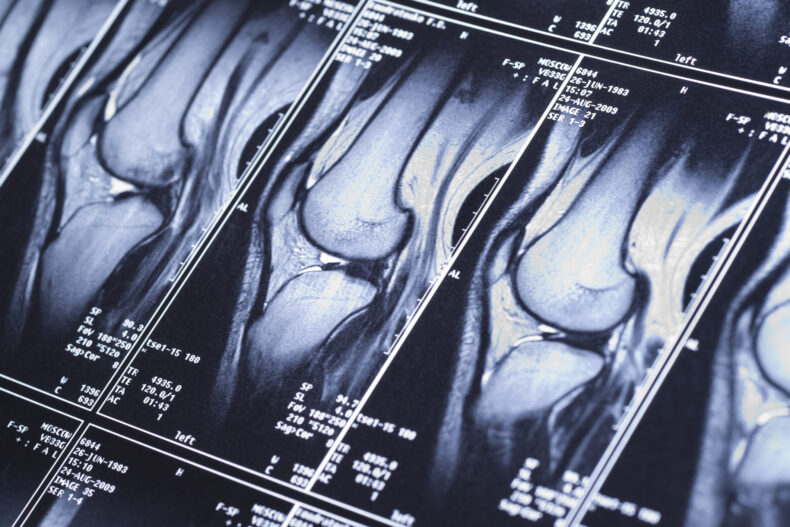

Si el médico sospecha un desgarro de menisco, pedirá una resonancia magnética (MRI). Esta prueba de imagen ofrece una visualización detallada de la anatomía interna, lo que permite confirmar si existe o no un desgarro meniscal.